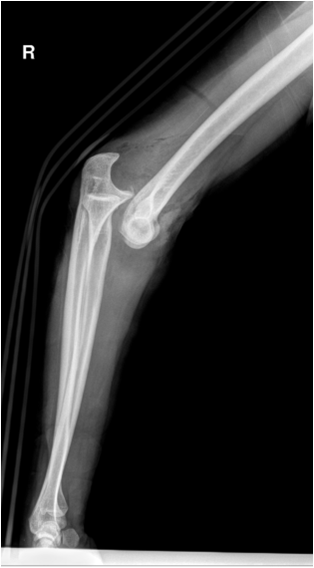

Notice the forearm, the hooked part, has moved up / the humerus, the ball part, has moved down.